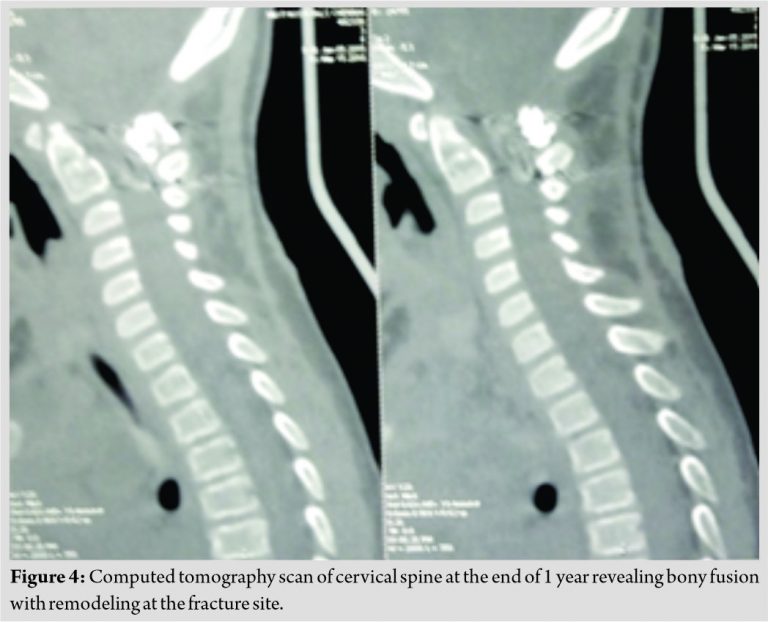

At a 1-year follow-up, CT scan of the cervical spine revealed excellent remodeling at the fracture site with bony posterior fusion at C1-C2 (Fig. 4). She had terminal limitation of rotations of the neck, but sagittal alignment was satisfactory.

Odontoid process fractures in the pediatric population are a rare entity, and the literature is sparse, with only a few cases reported [3,6]. It is unusual to have bony injuries below the age of 8 years due to relative elasticity of the growing spine [7]. The axis is the most commonly involved vertebra in children and odontoid synchondrosis fractures are usually seen in patients <7 years of age [8]. The management of such fractures in the pediatric population remains unclear. The current recommendations on the management of such an injury include high degree of suspicion focusing on symptoms, lateral cervical spine radiographs, and sagittal CT scan sections. Reduction and immobilization in an external orthosis or surgical stabilization for unstable cases have been reported. Fulkerson et al. in their case series reported a higher failure rate of certain odontoid fractures with external immobilization alone [9]. They considered a significant displacement of the odontoid of 11–100%, angulation of>30°, and clinical evidence of upper cervical spinal cord injury as indications for surgical intervention [9]. In our patient, there was significant displacement of the odontoid (approximately 70%) with C1-C2 subluxation which was associated with >30° angulation approaching the current consensus for the surgical fixation. There was a step deformity in her immediate post-operative radiograph which remodeled well by the end of 1 year. Excellent remodeling potential of the pediatric cervical spine has been reported by Bhagat et al. following in situ fusion in similar fractures in children[10].